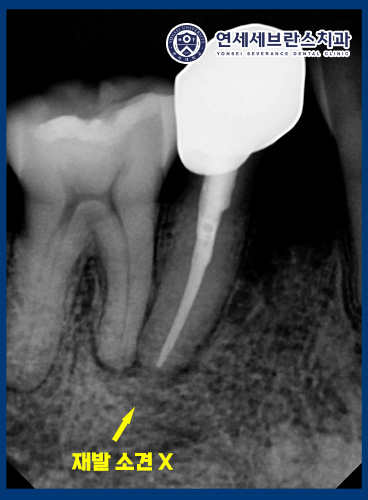

그리고 1년 6개월 뒤

정기 검진을 위해

다시 내원하셨습니다.

방사선 사진상 뿌리 끝 염증의

재발 소견은 보이지 않았으며,

이전에 염증으로 비어 보이던 부위가

새로운 뼈로 거의 차오른

모습을 확인할 수 있었습니다.

임상적으로도 통증이나 부종 없이

안정적인 상태를 유지하고 있어

치료가 성공적으로 유지되고 있음을

확인할 수 있었습니다.